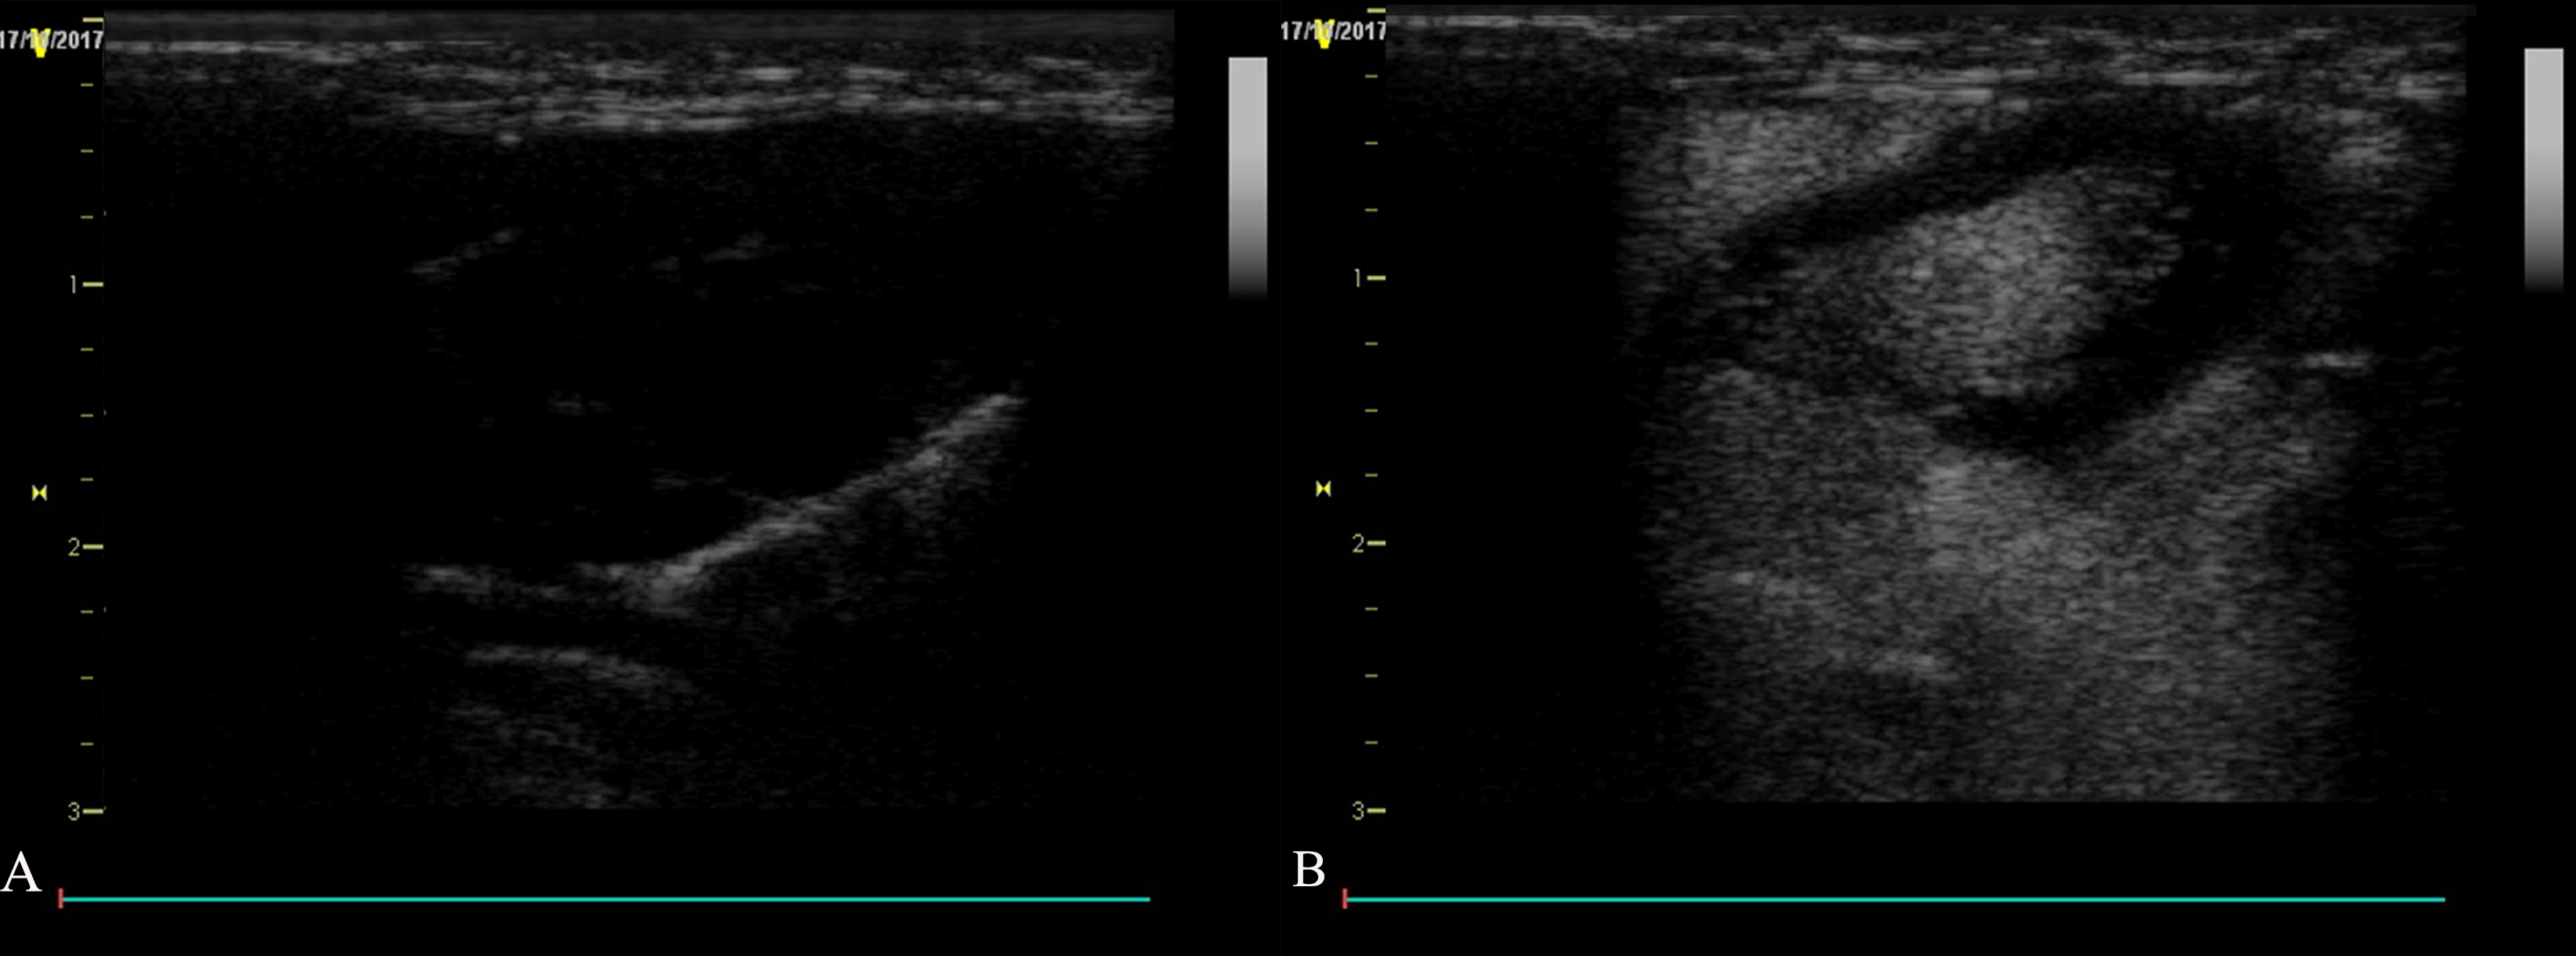

In order to verify the presence of atherosclerotic plaques, HE staining and contrast-enhanced ultrasound (CEUS) examination were used. In the experimental groups, foam cells were observed under the lesioned intima. The surface fibrous cap structure was broken, the elastic fibers were damaged and thinned, the thickess of media was increased with augmanted smooth muscle cells number and presence of foamy cells, and plaques were observed protruding into the lumen (Fig. 2A). The rabbit endothelial cells in the control group were intact (Fig. 2B).

Fig. 2.Formation of vulnerable plaque in rabbit atherosclerosis. (A) HE

staining of carotid atherosclerotic plaque in rabbits. (B) HE staining of carotid

artery in rabbits of control group (400

CEUS showed that the carotid artery

intima-media thickness (IMT) was thickened 0.03 mm, and the color Doppler flow

signal was well-filled at week 4. At week 8, the carotid artery IMT was thickened

more, and some rabbits had small plaques protruding into the lumen. Color Doppler

flow imaging (CDFI) showed a filling defect of blood flow at the plaque at the

week 8 and week 12, and the diameter stenosis rate was less than 30% (Fig. 2C,D).

Compared with the preoperative findings, the difference was statistically

significant (t = 24.96, p